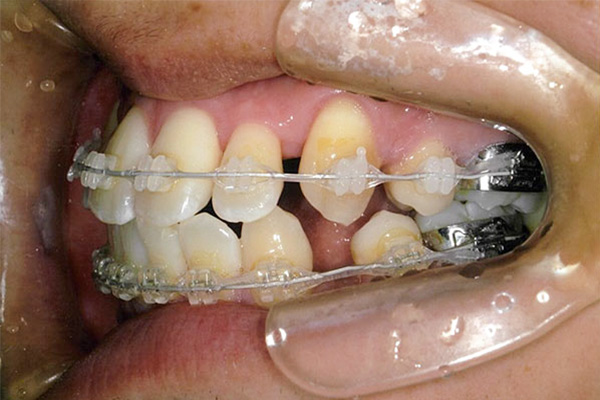

1年後